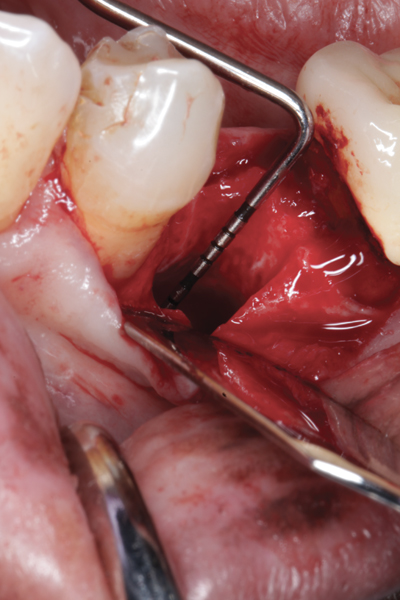

Fig 1. (Case 1) Tooth No. 19 manifested a buccal fistulous tract. Probing depth on the buccal was 8 mm.

Fig 2. Buccal flap elevated exposing buccal plate defect.

The four presented cases shown in Figure 1 through Figure 25 were all treated in a similar manner as outlined in detail in the captions for the first case (Figure 1 through Figure 11). In all four cases, teeth with pathosis were removed, buccal and lingual flaps were elevated, and sites were surgically debrided. A Cytoplast d-PTFE barrier was sized and inserted usually under the buccal flap, the bone graft was added, the barrier was then tucked under the lingual flap, and the flaps were sutured. Bone grafts were used in all of the cases, because buccal bony plates were resorbed and the bone graft helped support the barrier.